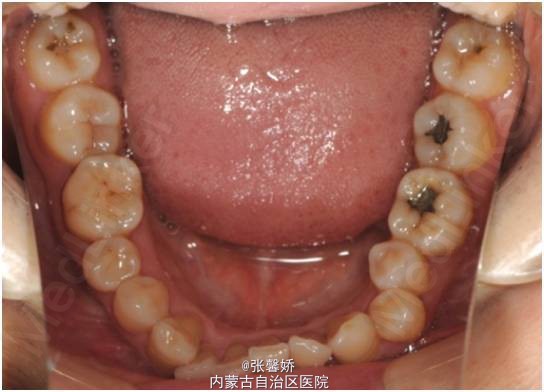

上中线右偏1mm,A2、D4反合,A2、B2畸形牙偏小,拥挤度上颌4mm、下颌6mm。Spee曲线:左侧3mm,右侧2.5mm

牙列中度拥挤;A2、D4反合 处理:时代天使隐形矫治器矫治 拔除C8、D8 适当下前牙邻面去釉 排齐整平上下牙列,改正A2、D4反合 治疗时间2年左右,矫治后牙齿排列整齐,咬合关系良好,患者满意。

一年后随访,患者咬合关系仍稳定,尖窝锁结良好。 隐形矫治适应证的选择很重要,适合中低难度的成人病例,患者的配合和依从性要求较高。 此患者术前全景片可见多个充填物,为龋易感患者,而且牙周也不是很好,隐形矫治没有拖槽更利于患者口腔卫生的维护,防止龋病的发生和牙周病的加重。